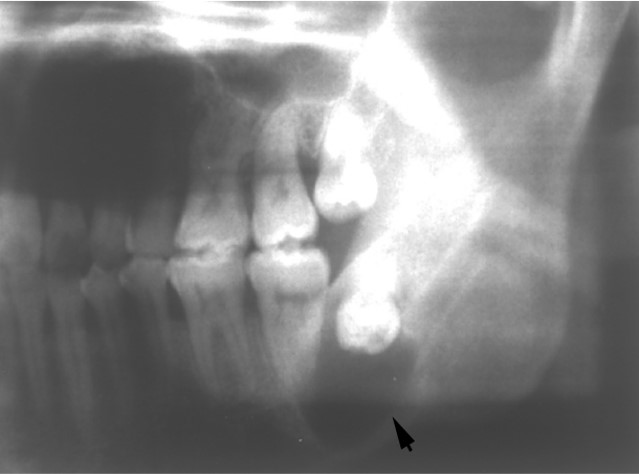

多发生于10~39岁患者,男性多见,以下颌第三磨牙最常见,多为恒牙,囊肿生长缓慢、早期无自觉症状,X线表现为圆形透射区,边界清楚,囊腔内含一个未萌芽的牙冠(图13.1-1)。

图13.1-1 含牙囊肿(X线)